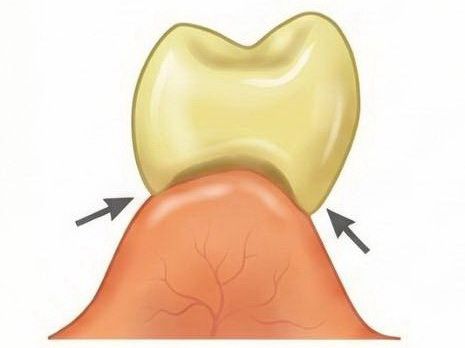

Răng giả nhịp cầu dạng yên ngựa (Saddle Pontic)

- Tiếp xúc: Mặt đáy răng giả có dạng lõm, phủ kín và ôm trọn sống hàm còn lại, tương tự như yên ngựa đặt trên lưng ngựa.

- Đặc điểm: Tạo ra vùng tiếp xúc rộng và lớn với niêm mạc ở cả mặt ngoài và mặt trong của sống hàm.

- Thực tế trong lâm sàng: Nhịp cầu loại này có diện tiếp xúc với niêm mạc quá rộng. Dù nhìn bên ngoài rất thẩm mỹ vì ôm sát sống hàm, nhưng nó tạo ra một “vùng chết” không thể làm sạch bằng bàn chải hay chỉ nha khoa dẫn đến vi khuẩn tích tụ dưới đáy nhịp cầu sẽ gây viêm nướu mạn tính, hôi miệng và tệ nhất là tiêu xương ổ răng của các răng trụ. Mình khuyên anh em nên tránh nhịp cầu loại này nếu không muốn bệnh nhân quay lại bắt đền vì cầu răng hôi và viêm..